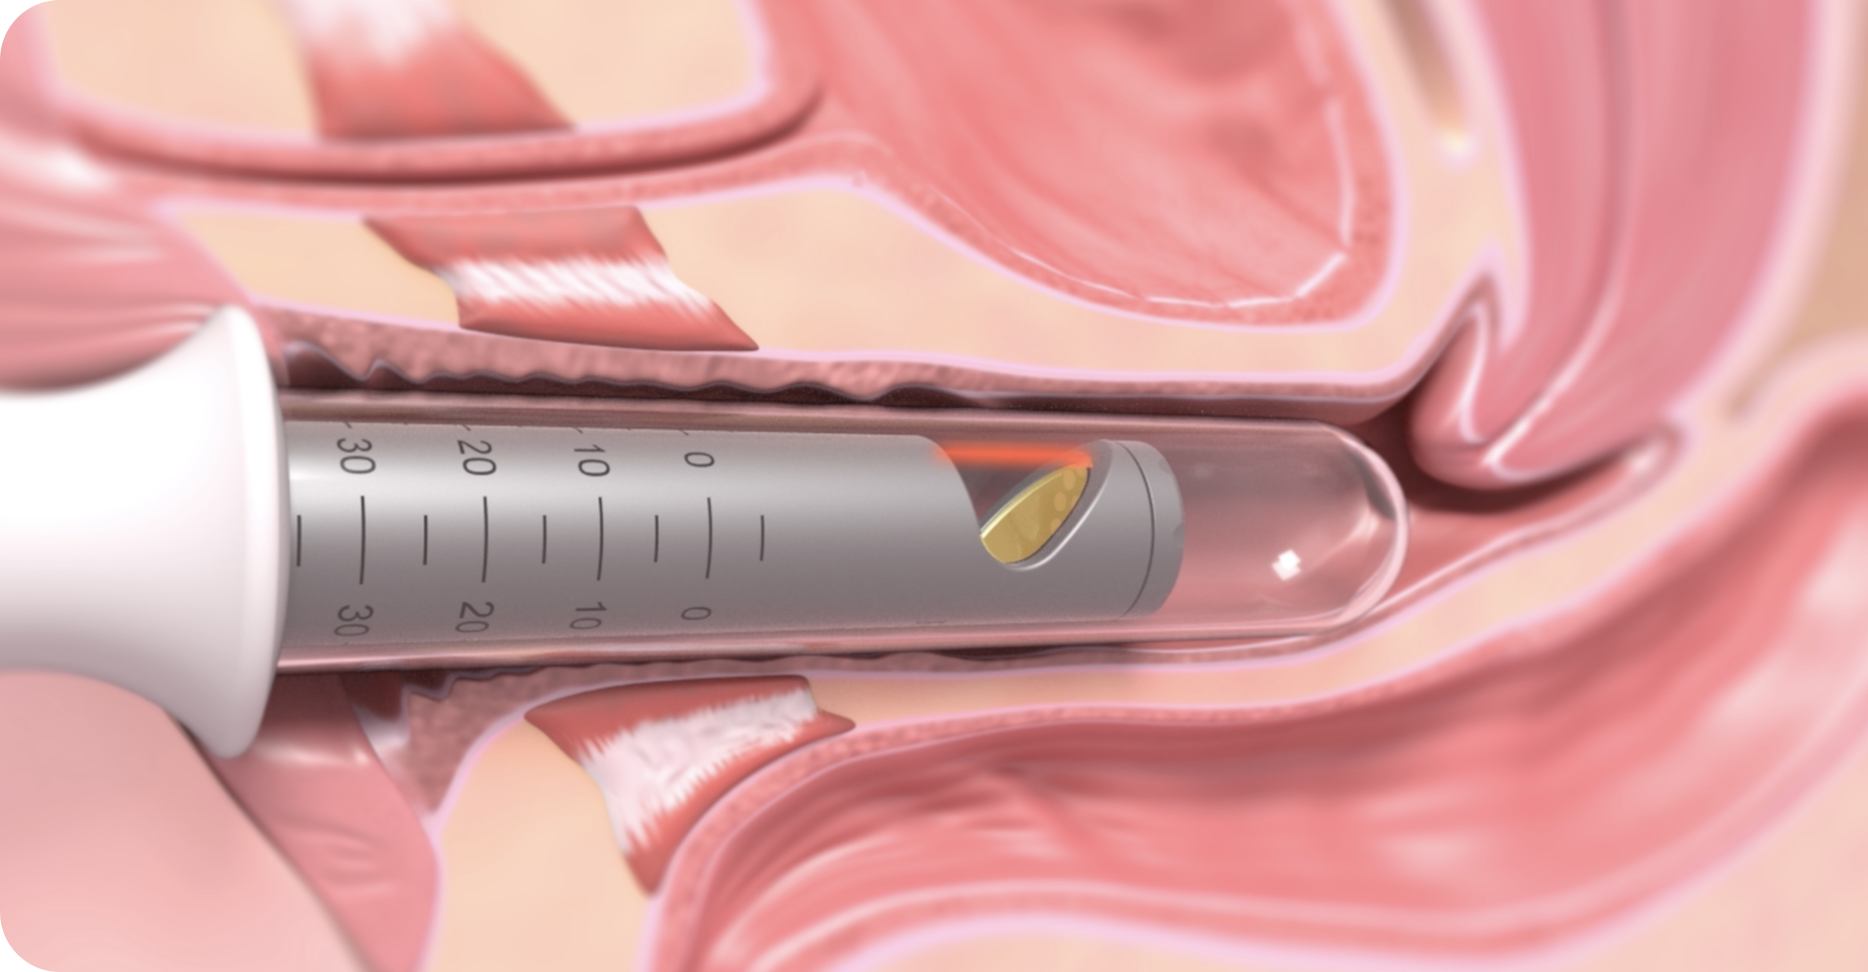

メスを使わない注入治療

切開を伴わず、ヒアルロン酸を膣壁に注入するだけの施術のため、身体への負担が少なく、初めての方でも受けやすいのが特長です。

膣ヒアルロン酸注入の方法と違い

① 部分注入(Gスポット周辺に注入)

Gスポット周辺にヒアルロン酸を注入し、膣粘膜に厚みをもたせる方法で、性感帯の膨らみを作ることで、刺激を感じやすくなる可能性があります。膣のゆるみよりも、快感度の向上を希望する方に適しています。

② 円周注入(膣の締まり感向上)

膣の周囲に均等に注入し、膣壁にボリュームをもたせる方法で、膣粘膜のハリを高め、膣のフィット感を向上させる可能性があります。

STEP02 麻酔

局所麻酔をおこないます。※局所麻酔は手術のご料金に含まれています。

STEP03 手術

手術中は麻酔が効いているため、痛みを強く感じることはありません。